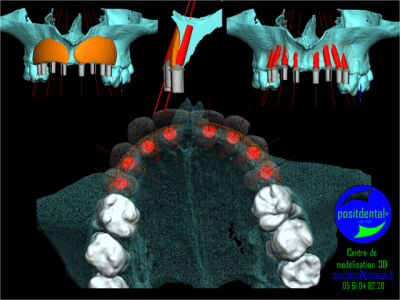

longueur des vis, façon de procéder, prévision de l'ouverture etc... ceci est facilité par le fait de la simulation 3D.

La suite, si tout se passe bien, sera préparation par biobank en salle blanche de greffon tout prêt pour n'importe quel cas d'apres un fichier 3D.

Qu’il est plus aisé de former le greffon sur un modèle de reconstruction volumétrique du maxillaire qu’insitu

Que la précision manuelle directement à partir d’un bloc spongieux est aléatoire puisque l’ensemble doit être retouché après visage. Cela peut aussi provenir d’un manque de précision de la reconstitution 3D.

Que la préparation juste avant la chirurgie ne peut garantir un bloc exempt de particule provenant du modèle notamment lors du perçage où des copeaux peuvent pénétrer dans les trabicule.

merci Posit la reconstruction 3D était parfaitement fidèle et merci Raphaël Bardonnet (Biobank) le produit livré était parfait.

des images 3d très nettes posit et une planif irréprochable